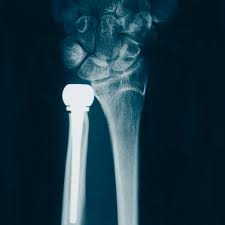

UHP

KLS Martins Ulnarhode-protese (UHP) brukes til å behandle lidelser i det distale radioulnare ledd. Disse er vanlige, og ofte forbundet med smertefulle begrensninger av underarmsrotasjon, krafttap og DRUJ-ustabilitet.Ulnarhode-protesen er utformet for å gjenopprette smertefri underarmsrotasjon, og kan også brukes for å gjenopprette riktig lengdeforhold mellom radius og ulna.

KLS Martin produserer også varianten UHP Spheric, som kan benyttes til å reparere mislykkede Sauve-Kapandji-prosedyrer ment til å behandle artroseforandringer i det distale radioulnare ledd. Denne prosedyren leder noen ganger til ustabilitet i ulnarstumpen, noe som igjen gir smertefulle gnisninger for pasienten. UHP Spheric er spesialdesignet for å korrigere problemer etter en Sauve-Kapandji-prosedyre.